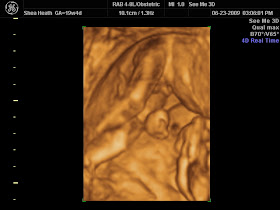

3d Ultrasound Port Jefferson Ny

Sonogram Clinic 3d 4d Ultrasound Centers In New York Usa